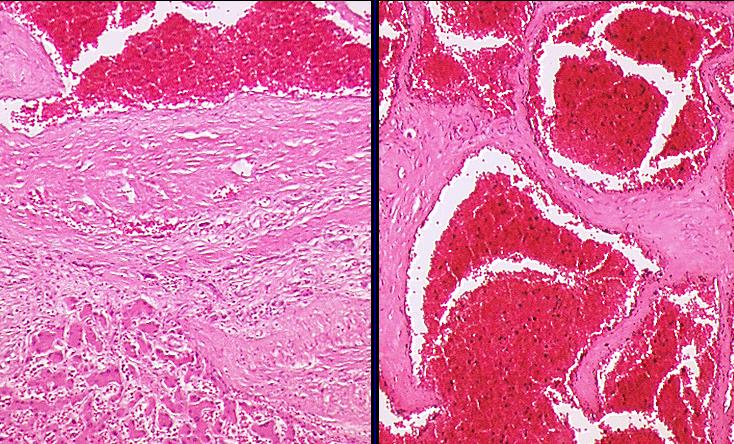

Histologie:

- gewucherte dilatierte Hohlräume

- von Endothel ausgekleidet, zum Teil auch mit

glatter Muskulatur

- prall mit Erythrozyten gefüllt

- von kräftigen bindegewebigen Septen

durchzogen

- oft Druckatrophie des umgebenden Gewebes